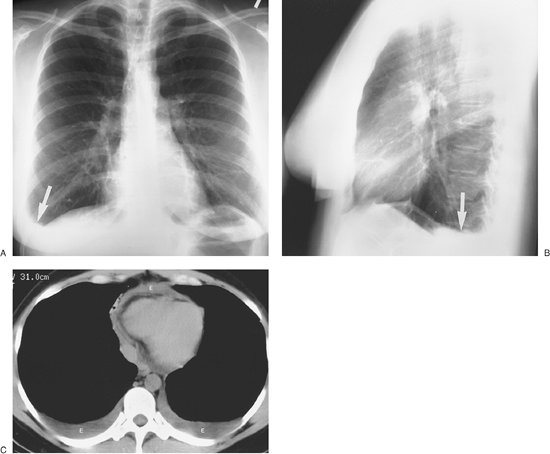

Malignant pleural effusions are usually the result of metastases (95% of cases) (16), with bronchogenic cancer accounting for 36% of cases, breast cancer for 25% (Fig. 9-16), lymphoma for 10%, and ovarian and gastric carcinoma for 5% or fewer (Fig. 9-17) (17). Although pleural effusion is often the major component of metastatic disease to the pleura, other findings include pleural nodules or extensive pleural thickening similar to that of mesothelioma. When the pleural metastases are unilateral, the CT findings may be indistinguishable from those of mesothelioma (18).

Malignant mesothelioma is a relatively rare primary tumor of the pleura. Approximately 80% of these lesions occur in individuals who have been exposed to asbestos (19). The lifetime risk for the development of mesothelioma in asbestos workers approaches 10%, and the average latency period is 35 years (20). Radiographic and CT findings include

P.148

nodular or irregular thickening of the visceral and parietal pleura, variable ipsilateral volume loss in the hemithorax, ipsilateral pleural effusion, involvement of the interlobar fissures and mediastinal pleural surfaces, and often fixation of the mediastinum (Figs. 9-18, 9-19, 9-20) (21). Approximately 18% of cases are associated with invasion of the chest wall (21).

FIGURE 9-16. Malignant pleural effusion. A: PA chest radiograph of an 83-year-old woman with metastatic right breast cancer shows a large right pleural effusion and interstitial lung disease. B: CT after drainage of right pleural fluid shows nodular thickening of the vascular structures and pulmonary septae on the right, characteristic of lymphangitic carcinomatosis.